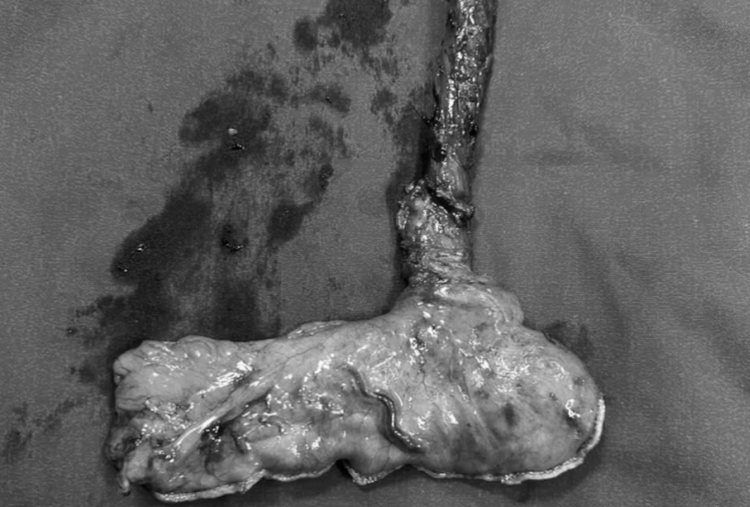

thuc-quan-2.png

Kết quả phẫu thuật nội soi ngực phải cắt thực quản cho bệnh nhân tại Bệnh viện Bãi Cháy - Ảnh BVCC